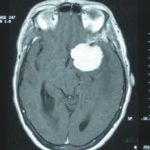

Cette masse peut entrainer notamment :

- Une irritation du cerveau qui se manifeste par une épilepsie

- Une compression voire destruction d’une partie du cerveau causant un affaiblissement ou une perte d’une fonction du cerveau

- Une augmentation de la pression à l’intérieur du crâne (espace inextensible à l’intérieur duquel vient s’ajouter le volume de la tumeur), ce qui va se manifester initialement par des maux de tête d’aggravation progressive qui vont s’associer à des nausées, des vomissements, des troubles visuels… Cet état peut aboutir à la perte de la vue dans les formes d’évolution lente et au décès dans les formes d’évolution rapide.